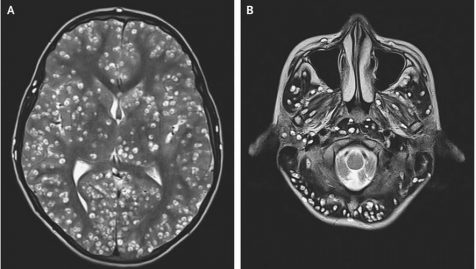

L’adolescent de 18 ans a été mené en urgence à l’hôpital car, il se plaignait de crises d’épilepsie. En plus de ses crises, il avait un œil tout gonflé, souffrait d’une douleur à l’aine droite et semblait être très confus. Une IRM cérébrale a été réalisée et a mis en évidence des dizaines de petits kystes logés dans son cortex cérébral. Ces tâches blanches en grand nombre étaient donc des kystes formés par des larves de ténia du porc. Suite à une échographie, les médecins ont également détecté des kystes dans son œil droit et son testicule droit, comme l’a rapporté le New England Journal of Medicine. Hélas, le jeune homme n’a pas survécu à cette importante infection et est décédé quelques heures plus tard.

l’IRM cérébrale montrant les kystes provoquées par les larves de ténia de porc